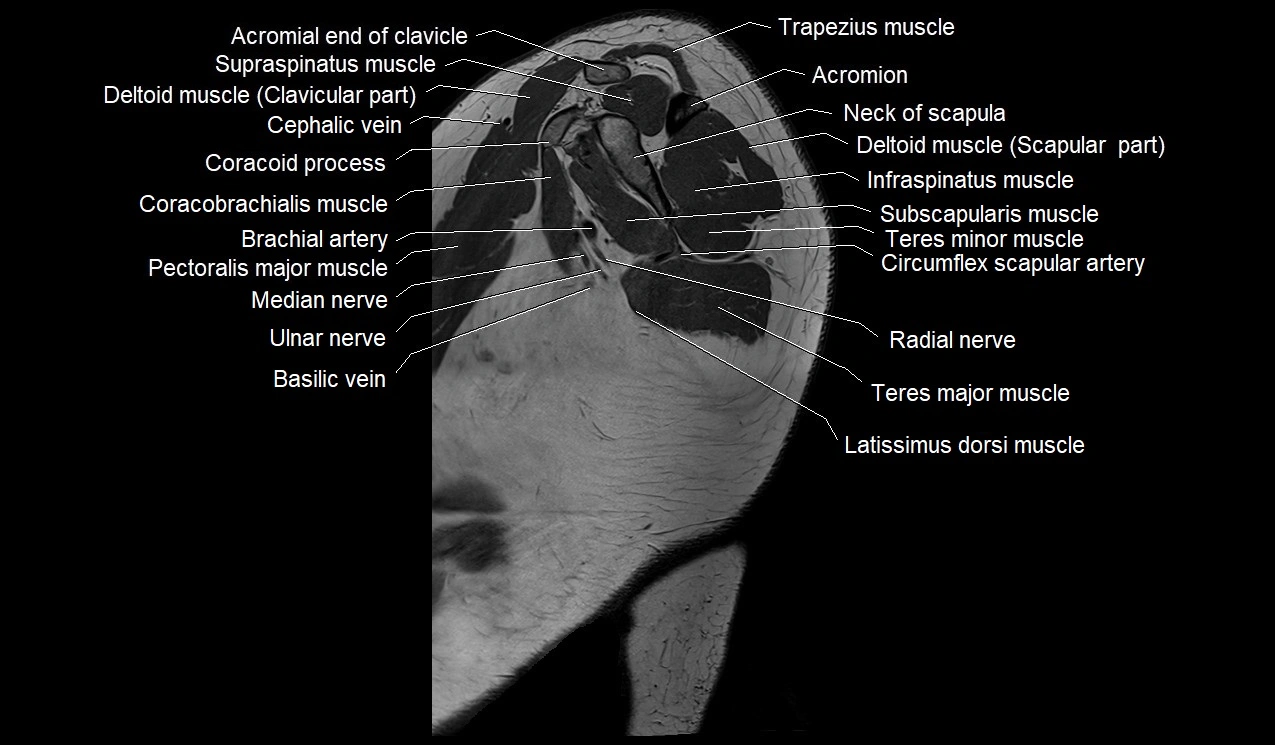

- Acromial end of clavicle

- Acromial part of deltoid muscle

- Acromion process of scapula

- Basilic vein

- Brachial artery

- Cephalic vein

- Clavicular part of deltoid muscle

- Coracobrachialis muscle

- Infraspinatus muscle

- Median nerve

- Neck of scapula

- Pectoralis major muscle

- Radial nerve

- Supraspinatus muscle

- Teres major muscle

- Teres minor muscle